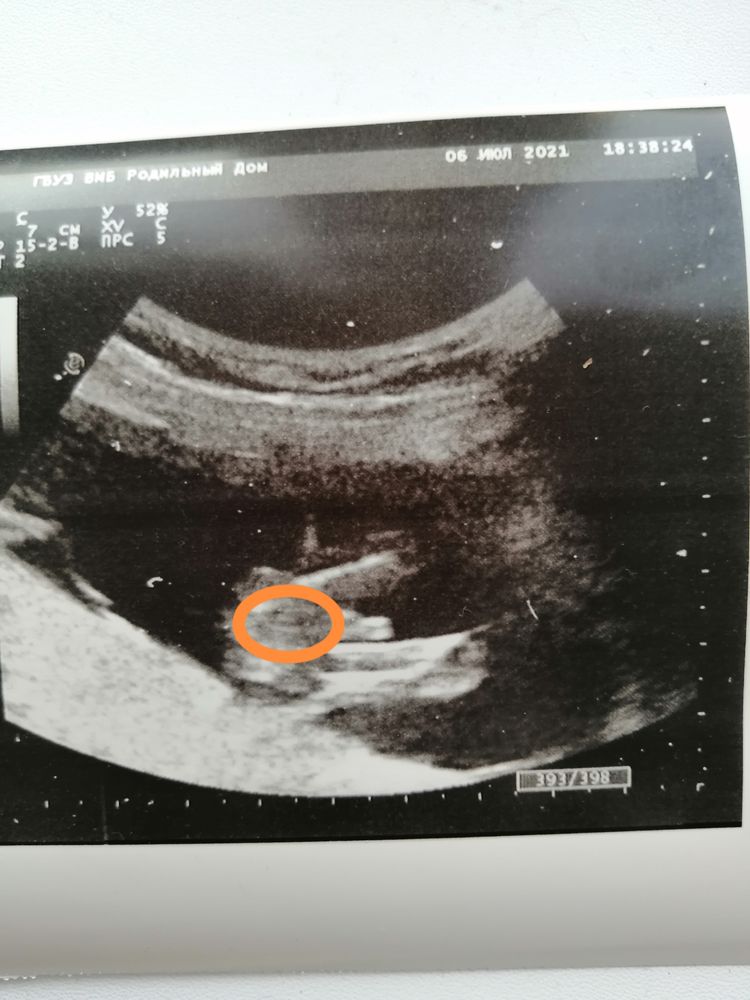

Мечты сбываются , посмотрите вот здесь, что выделено в кружок. Не похоже на девочку, а дальше там пуповина???? Изображение

Мила, да при чем тут этот кружочек, это может фото так искажать , это ж УЗИ . Там между ног всё понятно видно. У моих мужчин так же было. А у девочек там нечего такого нет, а по поводу пуповины, это всё ерунда. Мальчик у вас 💯

Мила, правда ведь похоже на девочку и пуповину? Или это просто я так вижу, потому что мечтаю о дочери?))))😂

Яна, Изображение посмотрите вот здесь, что выделено в кружок. Не похоже на девочку, а дальше там пуповина????

Кажется девчонка и пуповина , уж слишком большой перчик для 14 недель 😂

Кристина, очень надеюсь, что малышка))) Да и вообще даже не перчик, а какая-то яичковая цепь 😂🙈

Екатерина, посмотрите вот здесь, что выделено в кружок. Не похоже на девочку, а дальше там пуповина???? Изображение

Anastasia, дали снимок, сказали никак комментировать не буду, смотри сама, на втором скрининге скажу 🤷🏼‍♀️

Беременность третья, а ничего не меняется. Давайте разглядывать половой бугорок, девочки!) Девчонки подскажите???